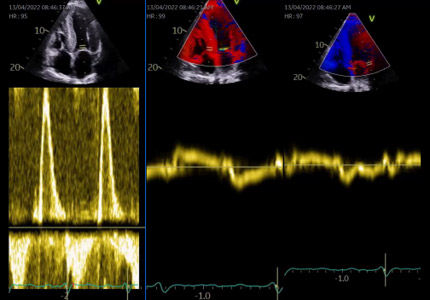

- Évaluation des pressions de remplissage (Figure 3), qui permet d’aider à adapter les doses de diurétiques ;

Figure 3 : HVG > 12 mm mais aussi VD en sous-costal. Profil diastolique de type trouble de la relaxation, possible dans l’amylose TTR à un stade pas trop sévère , comme ici où le strain VD est preserve > 23%